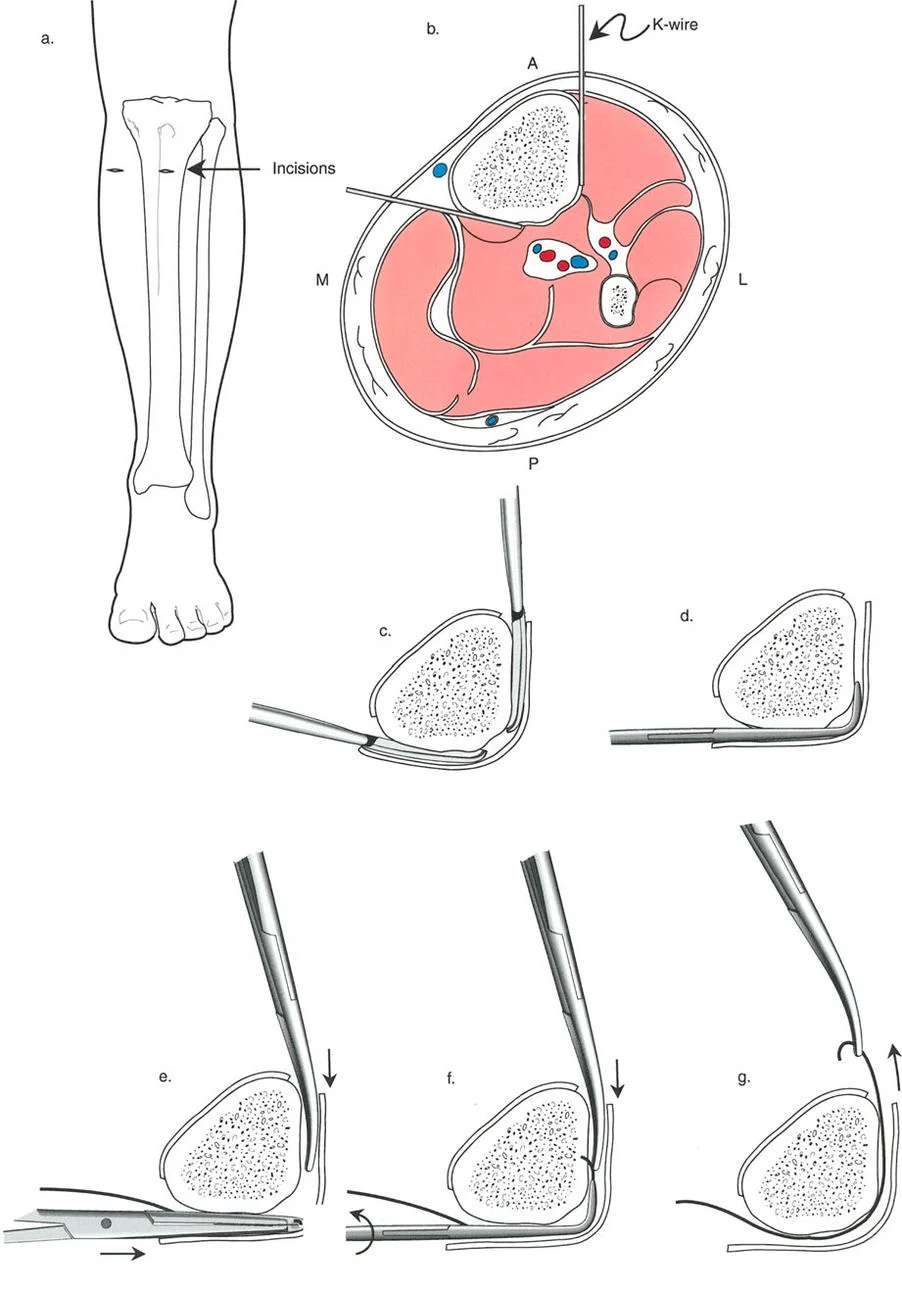

المفصلات القريبة من المفصل وقواعد قطع العظم (Osteotomy Rules)

عند التعامل مع التشوهات الواقعة بالقرب من خط المفصل - مثل التقوس الشديد في الجزء العلوي من الساق (مرض بلونت) أو التشوه الفحجي في الجزء السفلي من عظم الفخذ - يصبح وضع الجهاز مقيدًا هندسيًا. إن المتطلبات البيولوجية للحفاظ على كبسولة المفصل، وتجنب وضع الأسلاك داخل المفصل، ومنع التهاب المفاصل القيحي، غالبًا ما تجبر الجراح على وضع الحلقة المرجعية على مستوى مختلف تمامًا عن مركز دوران الانحراف (CORA) الفعلي.

تحدي مركز دوران الانحراف (CORA) القريب من المفصل

لمطابقة مفصلة المثبت الخارجي مع المستوى الدقيق لمركز دوران الانحراف (CORA)، يجب غالبًا بناء المفصلة فوق أو تحت مستوى الحلقة الفعلية. يُعرف هذا في مبادئ بالي باسم تجميع المفصلة القريبة من المفصل (juxta-articular hinge assembly).

إذا كان مركز دوران الانحراف (CORA) يقع بالقرب من خط المفصل، فإن وضع حلقة إليزاروف القياسية عند هذا المستوى بالضبط مستحيل دون انتهاك مساحة المفصل أو شد الهياكل الكبسولية الحيوية. لذلك، يتم تثبيت الحلقة المرجعية بالعظم الكثيف أو العظم الطويل المتاح، ويتم بناء آلية المفصلة باستخدام قضبان ملولبة، ولوحات توصيل، ودعامات. ثم يتم "إنزالها" (أو رفعها) لتتطابق تمامًا مع مركز دوران الانحراف (CORA) الهندسي الحقيقي.

قواعد بالي لقطع العظم (Osteotomy Rules) في وضع الأجهزة

فهم قواعد بالي لقطع العظم أمر لا غنى عنه لتخطيط الإطار:

- قاعدة قطع العظم 1: عندما يمر قطع العظم ومحور تصحيح الانحراف (ACA) كلاهما عبر مركز دوران الانحراف (CORA)، فإن نهايات العظم ستنحرف دون ترجمة (انزياح). يتم استعادة المحور الميكانيكي، وتظل نهايات العظم متقاربة تمامًا، مما يخلق تصحيحًا كلاسيكيًا "إسفينيًا مفتوحًا" أو "إسفينيًا مغلقًا".

- قاعدة قطع العظم 2: عندما يمر محور تصحيح الانحراف (ACA) عبر مركز دوران الانحراف (CORA)، ولكن يتم إجراء قطع العظم على مستوى مختلف (غالبًا بسبب ضعف جودة العظم عند CORA أو مشاكل في الجلد)، فإن نهايات العظم ستنحرف وتخضع لترجمة محسوبة ومقصودة لإعادة محاذاة المحور الميكانيكي.

- قاعدة قطع العظم 3: (للاكمال) عندما يمر قطع العظم عبر مركز دوران الانحراف (CORA)، ولكن يتم وضع محور تصحيح الانحراف (ACA) خارج CORA، سيتم إنشاء تشوه ترجمة جديد، وهو خطأ شائع في وضع المفصلات غير المخطط له جيدًا.

في المنشآت القريبة من المفصل، غالبًا ما نعتمد على قاعدة قطع العظم 2. نظرًا لأنه لا يمكننا قطع العظم بأمان عند خط المفصل تمامًا (مركز دوران الانحراف CORA)، فإننا نقطع العظم في مستوى أدنى في منطقة الميتافيسيس. بعد تحقيق التصحيح الزاوي عبر المفصلات (محور تصحيح الانحراف ACA)، يتم إعادة محاذاة خطوط المحور الميكانيكي بشكل مثالي، ولكن نهايات العظم في موقع قطع العظم تتحرك بالنسبة لبعضها البعض.

قيود الأسلاك والدبابيس في القاعدة 2

لتحقيق هذه الترجمة الضرورية والمقصودة بسلاسة باستخدام إطار دائري كامل الأسلاك، يلزم استخدام أسلاك الزيتون المعاكسة (counter-opposed olive wires). تعمل أسلاك الزيتون كقوى سحب ديناميكية، تسحب قطعة العظم على طول الحلقة أثناء فتح المفصلات. بدون أسلاك الزيتون، سيبقى العظم ثابتًا بينما تتحرك الحلقة عبر الأنسجة الرخوة، مما يسبب نخرًا شديدًا في الجلد.

على العكس من ذلك، إذا تم استخدام دبابيس نصفية (مسامير شانز)، فإنها تقيد العظم بطبيعتها بالحلقة. نظرًا لأن الدبابيس النصفية هي أذرع صلبة (مثبتة من طرف واحد بالحلقة ومغروسة في العظم من الطرف الآخر)، فإنها لا تسمح للعظم بالانزلاق على طول محور السلك. هذا يجعل أسلاك الزيتون غير ضرورية للترجمة في منشآت الدبابيس النصفية، ولكنه يتطلب من الجراح التأكد من أن الدبابيس النصفية قوية بما يكفي (عادةً دبابيس بقطر 5 مم أو 6 مم مطلية بهيدروكسي أباتيت) لتحمل لحظات الانحناء الناتجة عن الترجمة.

نصائح جراحية للمنشآت القريبة من المفصل

| المبدأ | التطبيق السريري | تحذير / خطأ محتمل |

|---|---|---|

| التحقق من CORA | دائمًا تحقق من CORA الحقيقي في الأشعة السينية الطويلة للطرفين قبل بناء المفصلة. | الاعتماد على الأشعة السينية القصيرة للركبة سيؤدي إلى CORA غير دقيق وبالتالي سوء محاذاة. |

| ACA العمودي | تأكد من أن محور المفصلة (ACA) عمودي تمامًا على مستوى التشوه. | محور ACA مائل سيحدث تشوهًا ثانويًا غير مرغوب فيه (مثل تصحيح التقوس ولكن إحداث الانحناء الأمامي). |

| تخليص الأنسجة الرخوة | عند استخدام قاعدة قطع العظم 2، احسب الترجمة المتوقعة وتأكد من أن الأنسجة الرخوة يمكن أن تستوعبها. | عدم مراعاة الترجمة يمكن أن يتسبب في اصطدام العظم بالجلد، مما يؤدي إلى النخر. |

| تقابل الأسلاك | استخدم ما لا يقل عن سلكين زيتون متقابلين لكل قطعة إذا كنت تتجنب الدبابيس النصفية. | الأسلاك الزيتون الفردية ستسبب قصًا ودورانًا غير مرغوب فيه حول محور السلك. |